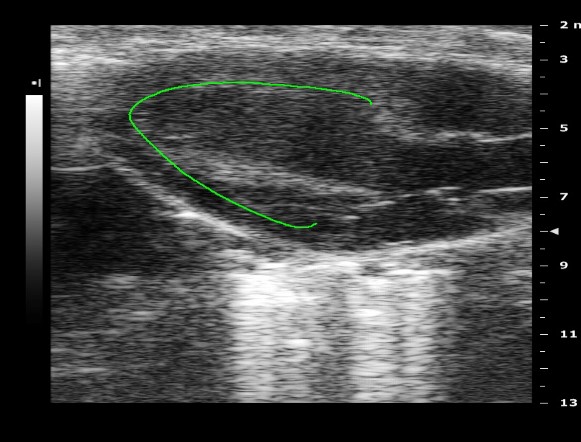

Normal Day-0 Preoperative Baseline Echo Data